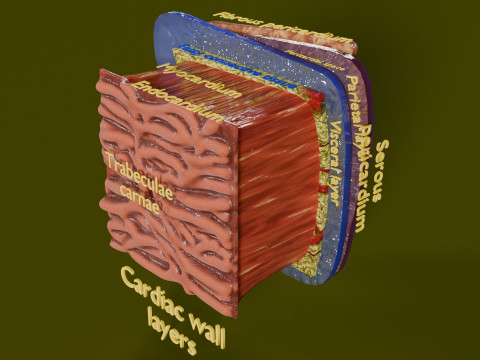

A blend model of brain along with its covering layers (meninges), skull bone and scalp labelled in detail and anatomically precise. The parts depicted are white, gray, pia, arachnoid, dura, bone, skin, fat, aponeurosis, periosteum, falx cerebri and more.